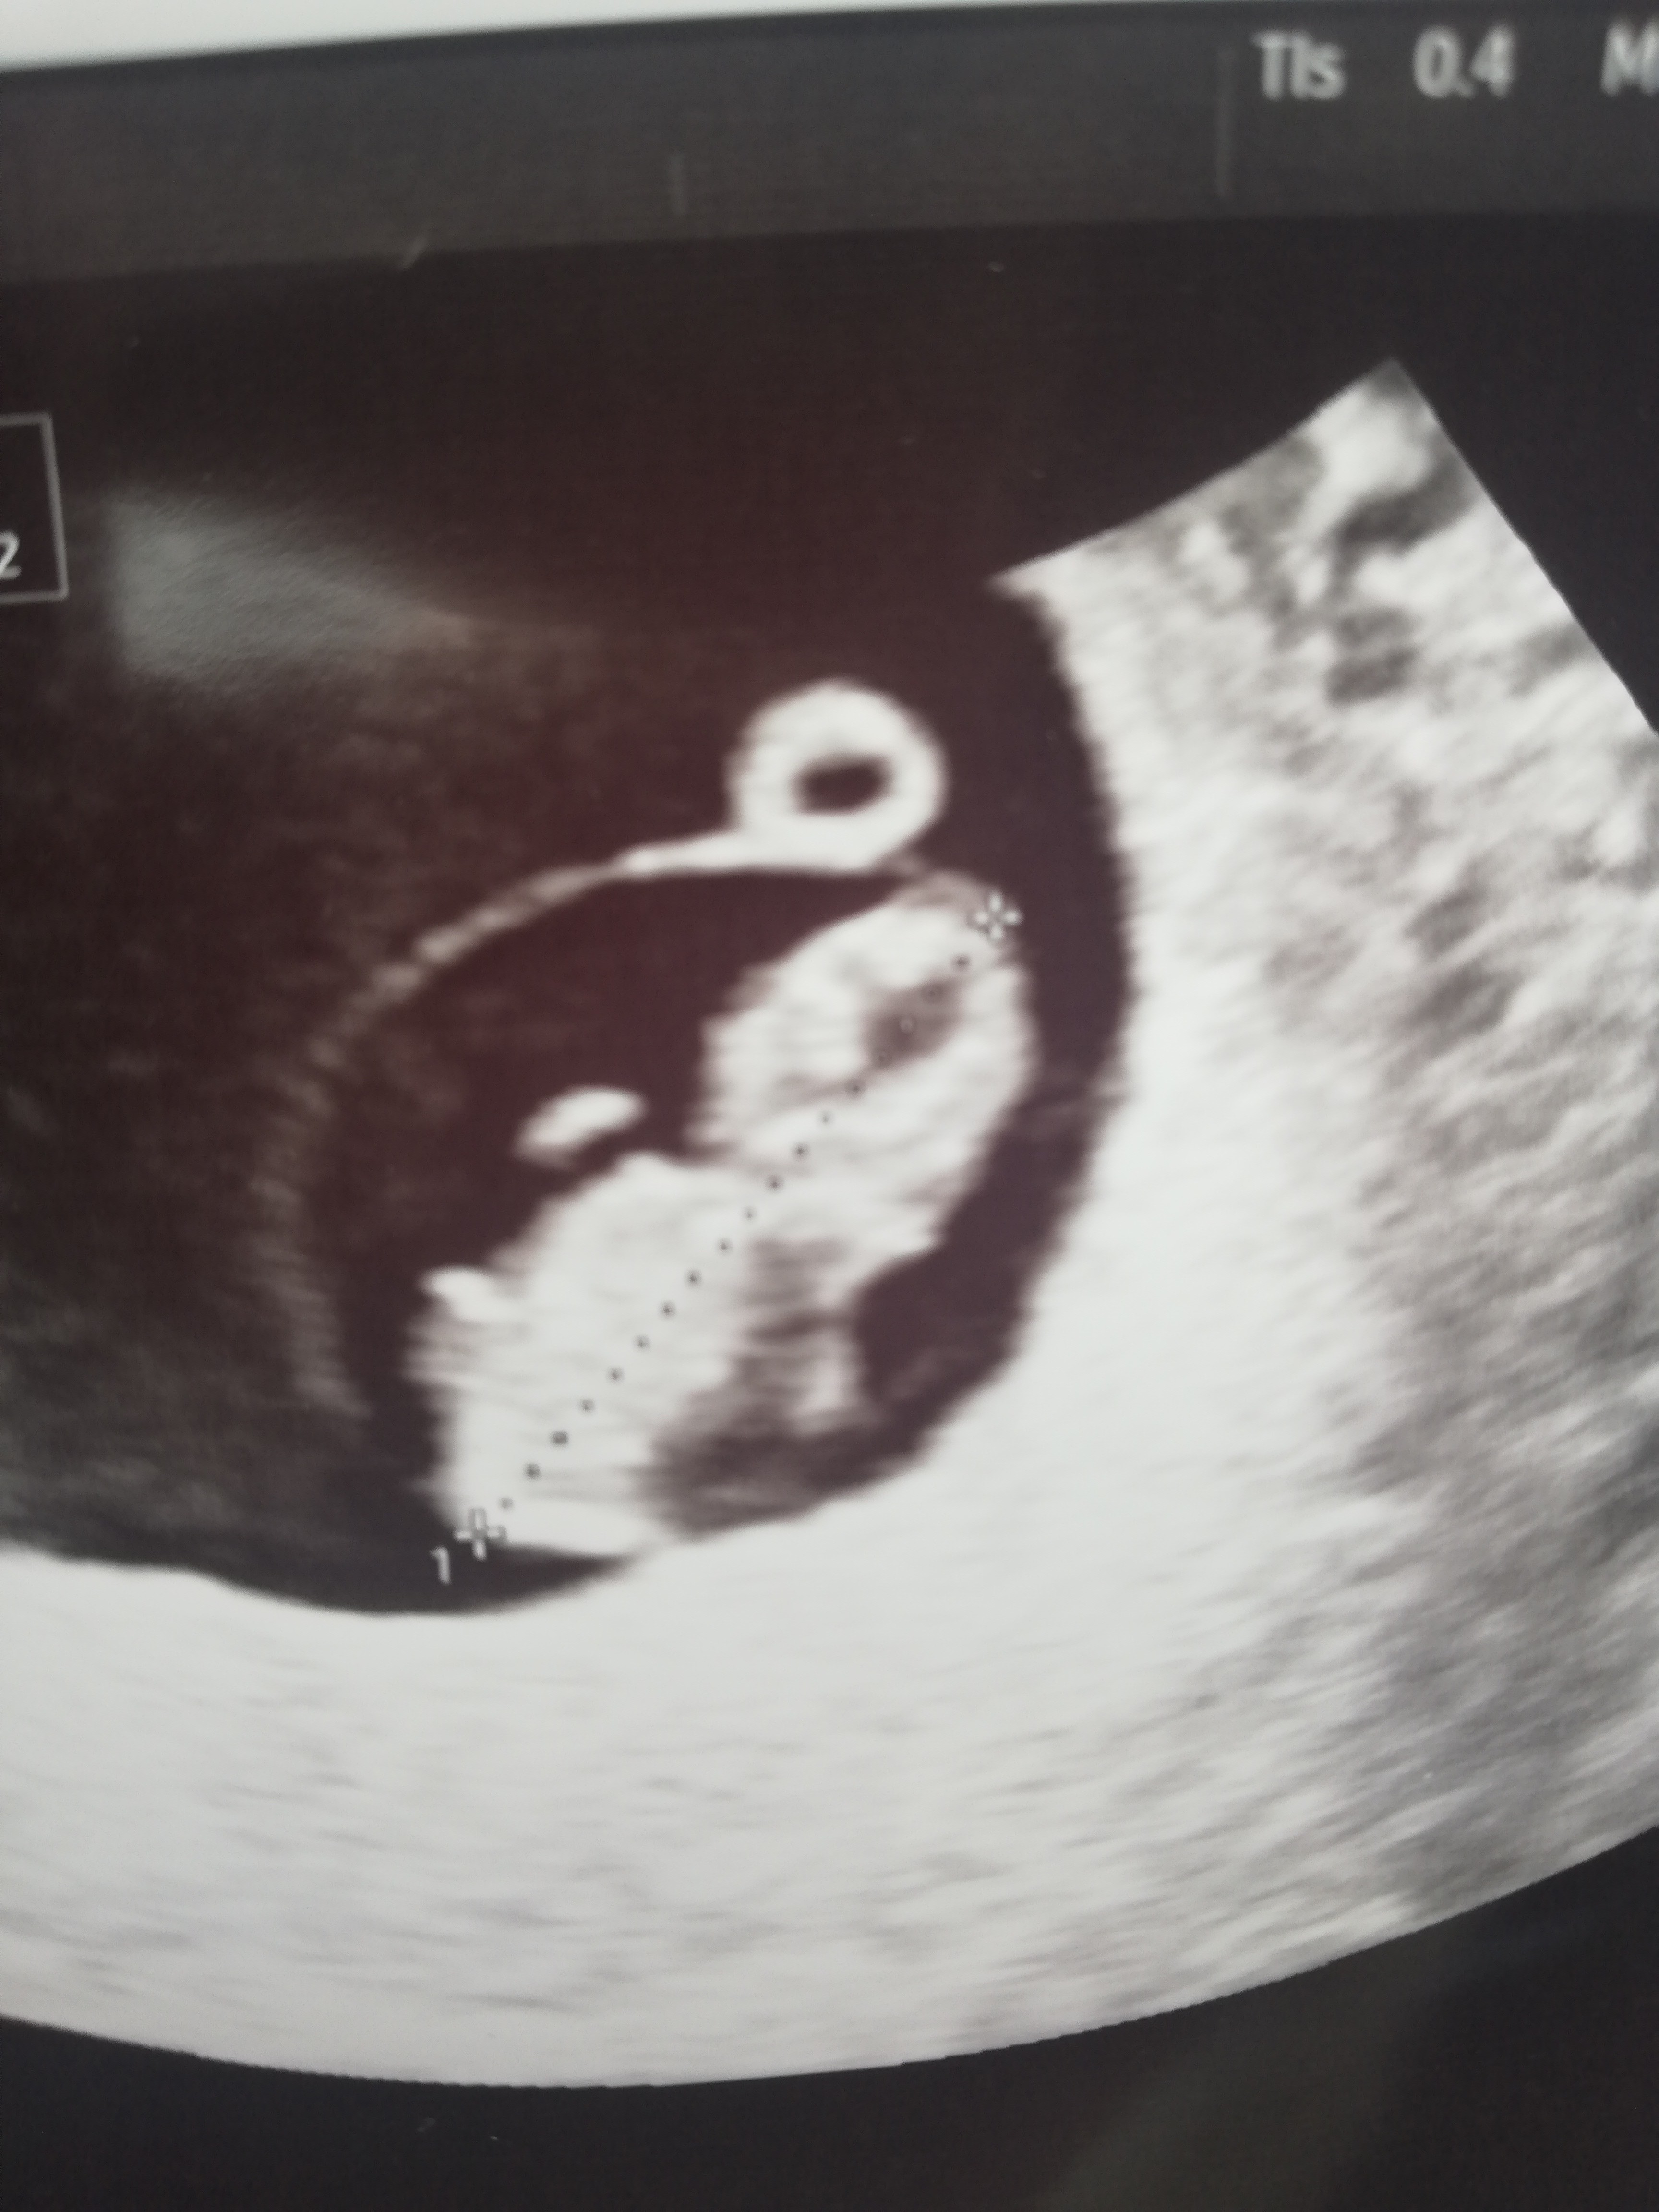

Już niezły ludzik

Ja byłam 7+1 to ten obraz nie był taki oczywisty

Teraz pójdę 9+2 to powinno być już ładnie widać

Cześć u nas 8+3![]()